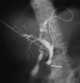

Carcinoma of ampulla

The ampulla of Vater, also known as the hepatopancreatic ampulla or the hepatopancreatic duct, is formed by the union of the pancreatic duct and the common bile duct. The ampulla is specifically located at the major duodenal papilla. [Source: Wikipedia ]